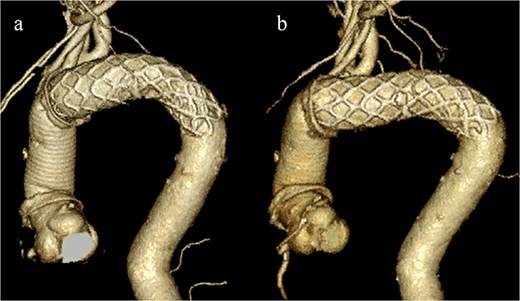

Given the ongoing hemoptysis, presumed aneurysmal expansion due to an occult endoleak, and the absence of any other obvious causes of hemoptysis, we determined that intervention for the aneurysm was necessary. TEVAR was performed using a right femoral artery approach. Initial angiography did not reveal contrast leakage into the sac (Fig. 3a). A 34 × 34 × 200 mm Gore Conformable TAG stent graft (W.L. Gore & Associates, Flagstaff, AZ, USA) was deployed to cover the distal edge of the FET. The second stent graft, a 34 × 34 × 150 mm Gore Conformable TAG stent graft, was deployed overlapping the first graft immediately after the left subclavian artery branch to cover the entire length of the FET (Fig. 3b). Considering the proximal migration, a type Ib endoleak was deemed the most likely cause. However, the possibility of a type III endoleak from the graft was also considered, so the stent graft was deployed to cover the entire area. The patient’s hemoptysis resolved completely postoperatively. A follow-up CT 2 years later showed a reduction in the aneurysm size from 56 to 44 mm (Fig. 4).

(a) Angiography performed from within the FET before deploying the stent graft showing no evidence of endoleak or aortobronchial fistula. (b) Angiography after stent graft placement. The bidirectional arrow shows the original extent of the FET insertion.